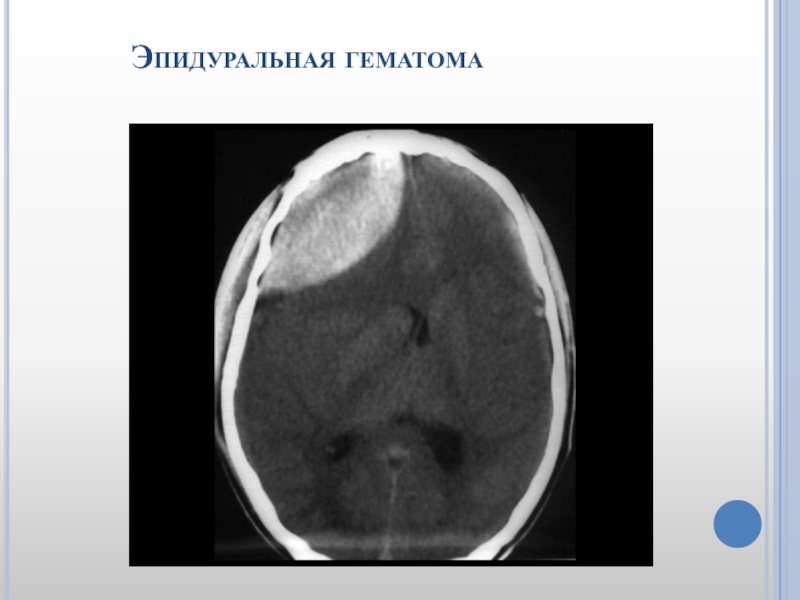

Слайд 38 Эпидуральная гематома

Слайд 39 Эпидуральная гематома

Слайд 40 Эпидуральная гематома

Эпидуральная гематома (в

виде линзы);